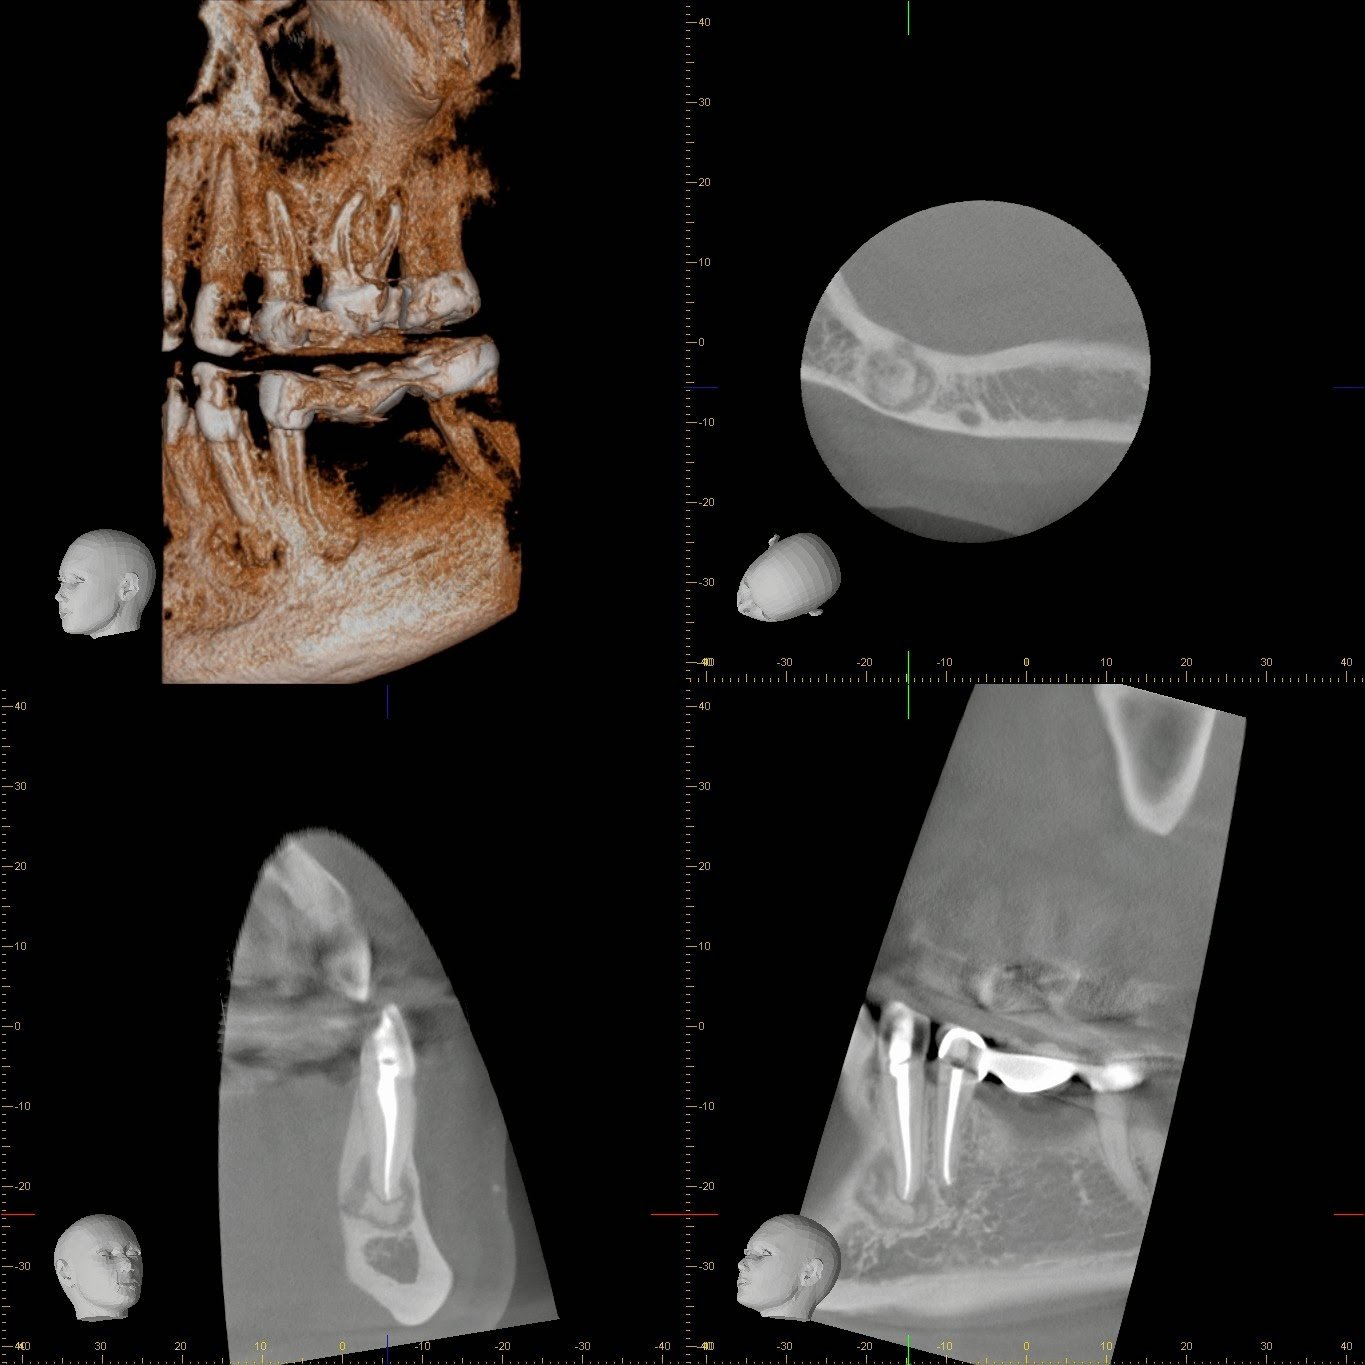

A 42 yr old, white, female presented for evaluation of #22. She was asymptomatic, with a prior RCT on #22. A large nodular, irregular, radiopacity found within a large radiolucent area on the periapical radiograph. Tooth is normal to palpation, percussion and probings.

DX: Prior RCT with possible periapical cemental dysplasia. Apical surgery recommended with biopsy.